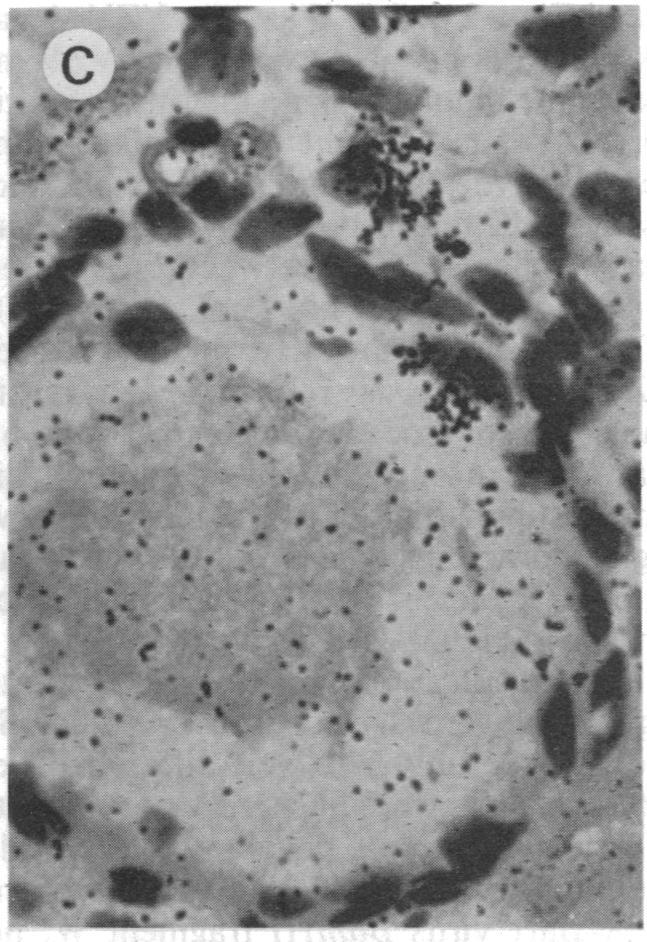

The cellular localization and viral transcription patterns of acute and latent varicella-zoster virus (VZV) infections of human sensory nerve ganglia were studied by in situ hybridization and compared with those of latent herpes simplex virus (HSV) infection. Trigeminal and dorsal root ganglia obtained at autopsy were hybridized with 35S-labeled single-stranded RNA probes homologous to VZV or HSV fragments. We have reported that HSV persists in human sensory neurons and expresses only one family of transcripts that overlap extensively with, but are opposite in polarity to, the mRNA encoding the immediate early protein termed infected cell protein 0 (ICP0). In the present study we find that latent VZV infection involves nonneuronal cells, and multiple, but not all, VZV genes are transcribed. In contrast, during varicella both neuronal and nonneuronal cells are infected, with all regions of the VZV genome analyzed being expressed. Thus, the patterns of gene expression and cellular locations of VZV and HSV infections of human ganglia differ. The differences may underlie clinical features that distinguish these infections.

通过原位杂交研究了人感觉神经节急性和潜伏性水痘-带状疱疹病毒(VZV)感染的细胞定位和病毒转录模式,并与潜伏性单纯疱疹病毒(HSV)感染的情况进行了比较。对尸检时获得的三叉神经节和背根神经节用与VZV或HSV片段同源的35S标记单链RNA探针进行杂交。我们曾报道HSV在人感觉神经元中持续存在,并且仅表达一类转录本,这些转录本与编码即刻早期蛋白即感染细胞蛋白0(ICP0)的mRNA广泛重叠,但极性相反。在本研究中,我们发现潜伏性VZV感染涉及非神经元细胞,并且多个但并非所有VZV基因都被转录。相比之下,在水痘期间,神经元和非神经元细胞均被感染,所分析的VZV基因组所有区域均有表达。因此,人神经节中VZV和HSV感染的基因表达模式和细胞定位有所不同。这些差异可能是区分这些感染的临床特征的基础。